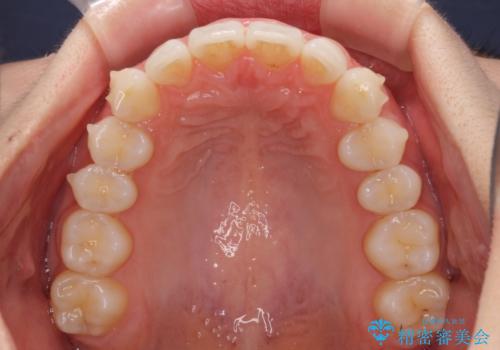

- 上下前歯の叢生を気にして来院された患者様です。

以前矯正をした後戻りということで、歯列不正はそれほど大きくなかったため、インビザライン・ライトを用いて矯正治療を行うこととしました。

インビザラインは1日に22時間を目安に装着していただきますが、装着時間が十分でないとシミュレーション通りに動かないことがあります。

前歯のデコボコが残っており、シミュレーション通りに動いていない部分がありましたが、再矯正であることやご本人の満足いくところまでデコボコが改善されたとのことで、治療を終了することとしました。